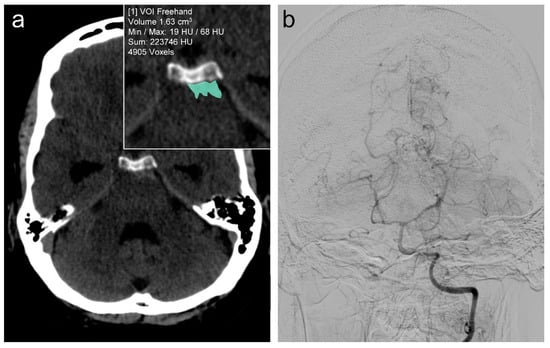

2.2. Data Collection and Analysis